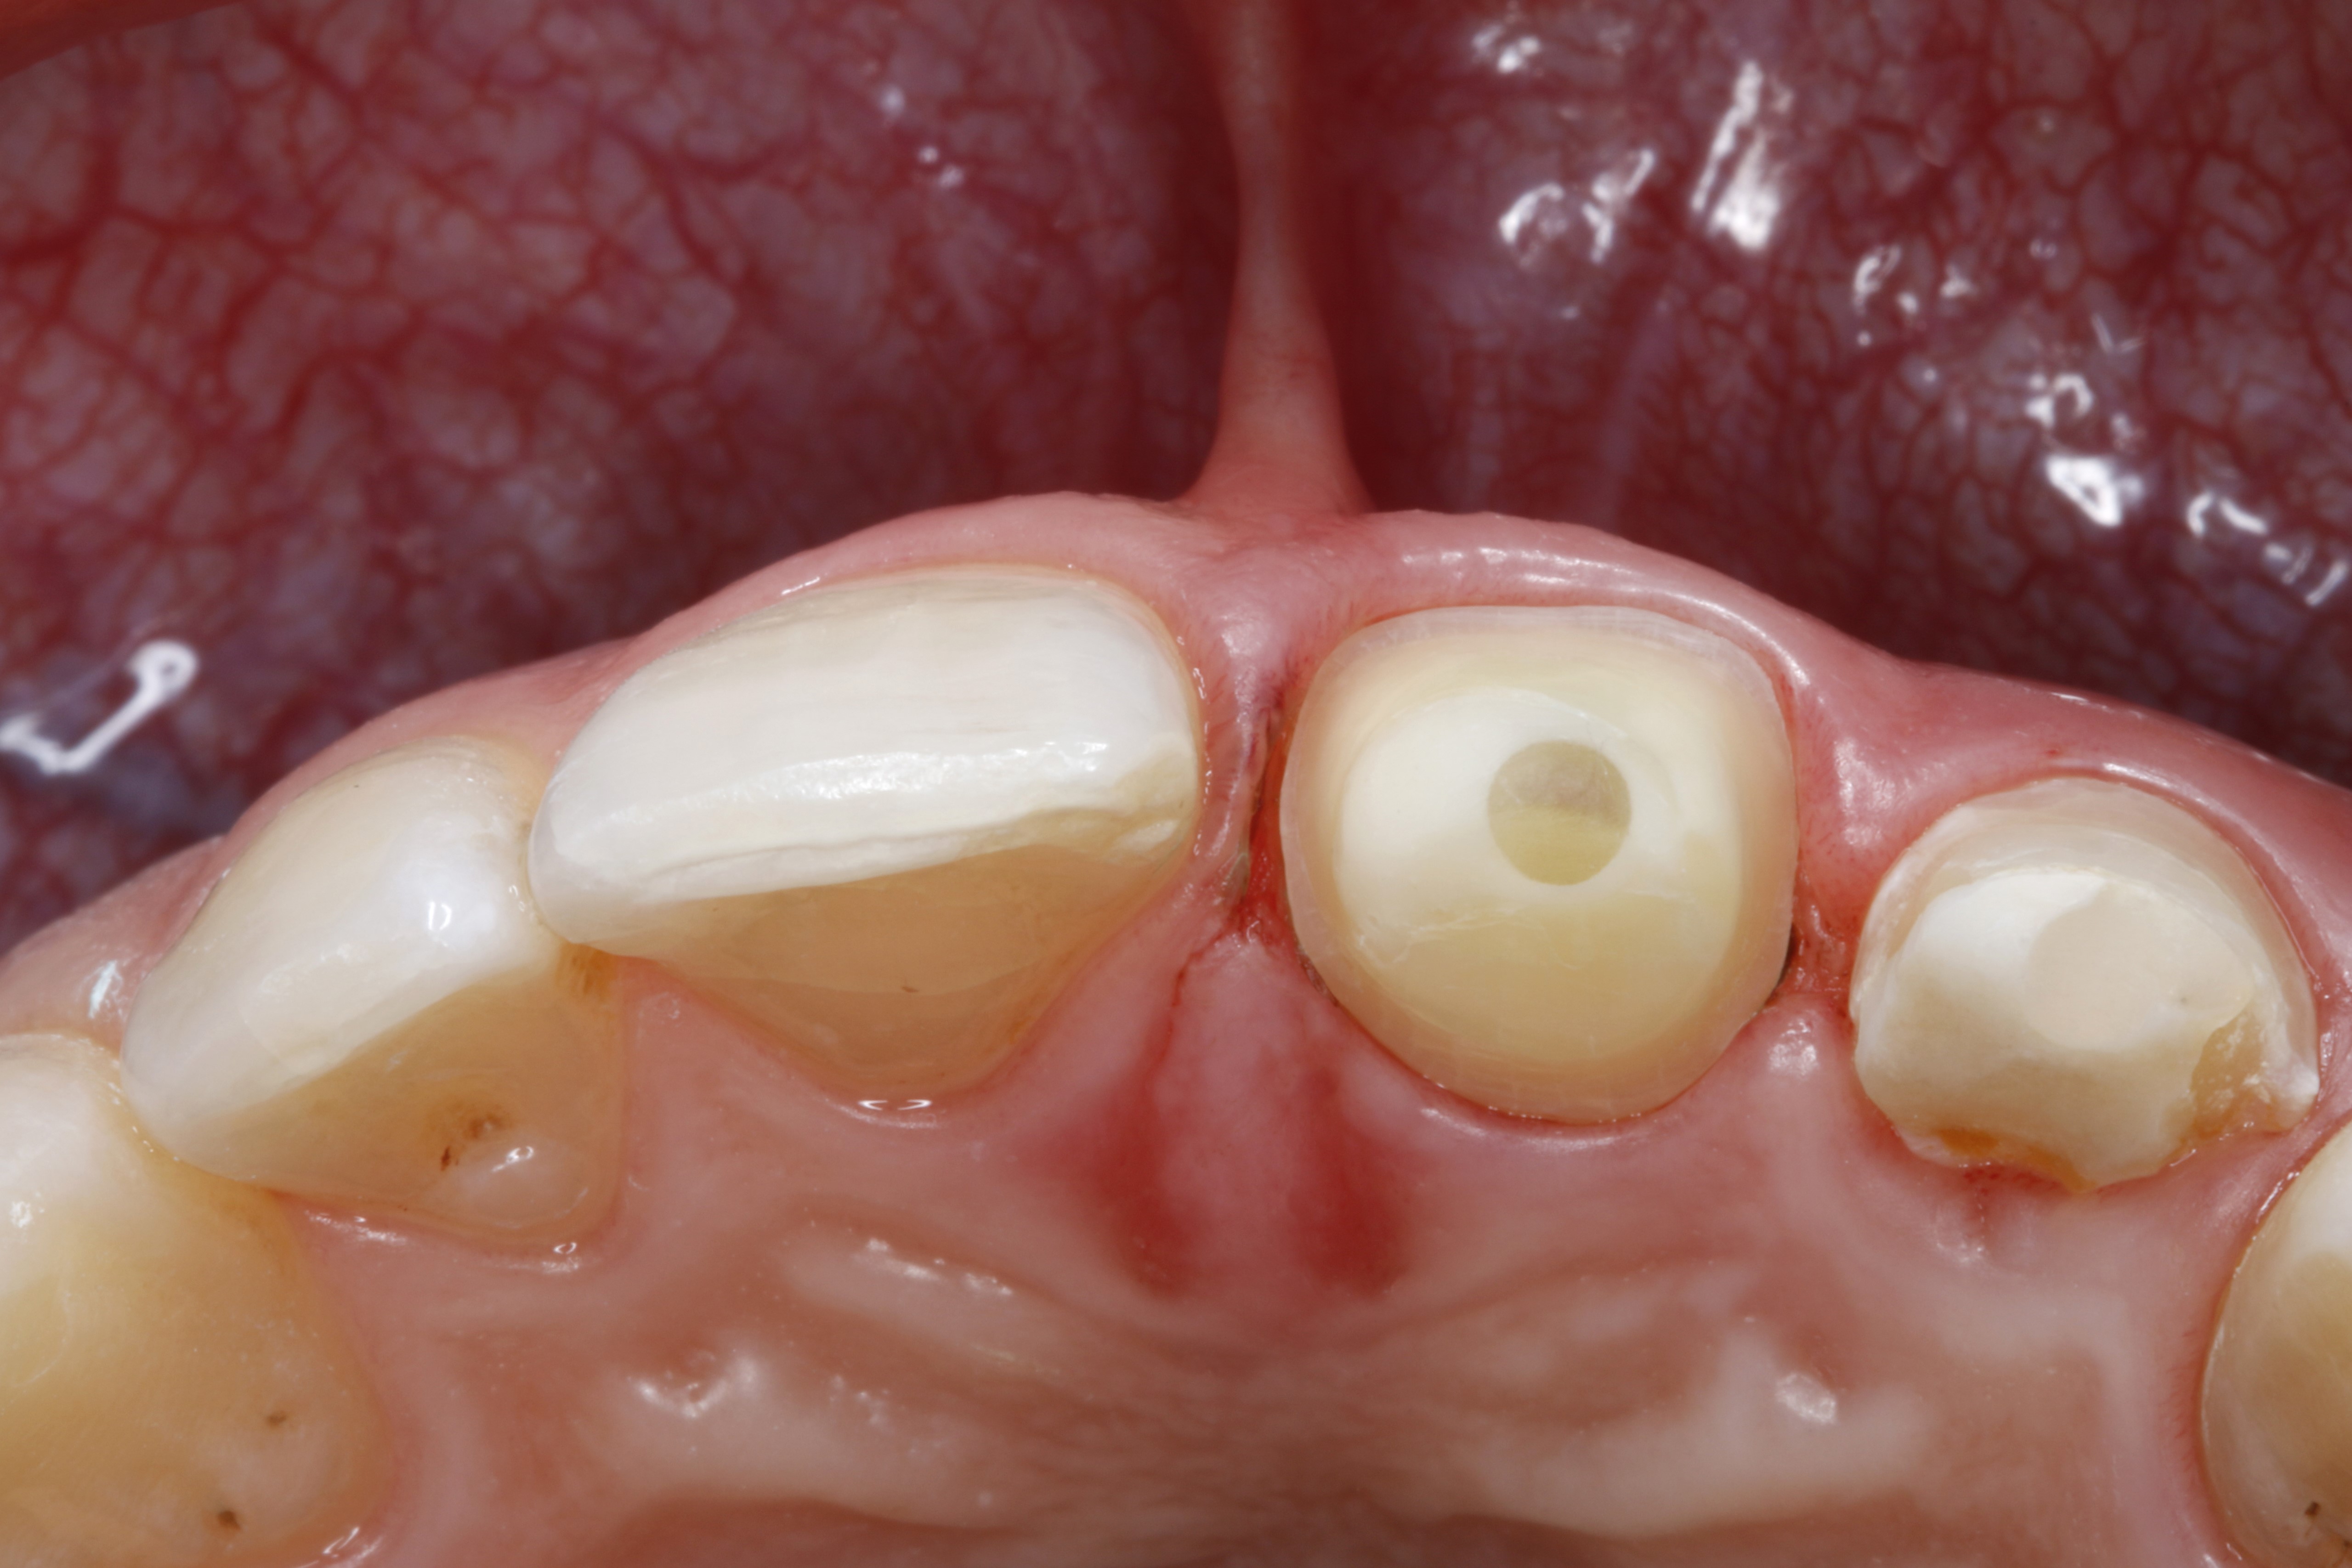

Rozpoznanie - złamanie zębów 21 i 22 na skutek urazu.

Ryc. 1. Sytuacja początkowa – złamane zęby sieczne szczęki po stronie lewej po urazie. Ząb 21 poddano leczeniu endodontycznemu. W zębie 21 przeprowadzono trepanację, do kanału korzeniowego wprowadzono jako tymczasowe zaopatrzenie wodorotlenek wapnia.

Ryc. 2. Sytuacja początkowa, widok od strony brzegów siecznych – widoczne głębokie, podniebienno‑dystalne złamanie zęba 22, uniemożliwiające odbudowę ze względu na niekorzystny przebieg płaszczyzny złamania. Z tego względu ząb zachowano tylko do czasu zaplanowanego usunięcia z natychmiastowym wszczepieniem implantu.

Ryc. 3. Sytuacja po opracowaniu zęba 21 do korony. Podczas kolejnej wizyty zaplanowano usunięcie zęba 22 i przeprowadzenie natychmiastowej implantacji. Do czasu wykonania docelowej rekonstrukcji, jako tymczasowe długoczasowe zaopatrzenie w okresie gojenia, należy wykorzystać wykonaną w pracowni protetycznej koronę na ząb 21, z przęsłem dowieszonym w okolicy zęba 22.

Ryc. 4. Ząb 21 od strony brzegu siecznego – widoczny zacementowany adhezyjnie, wzmocniony włóknem szklanym wkład koronowo‑korzeniowy (Rebilda Post, VOCO).